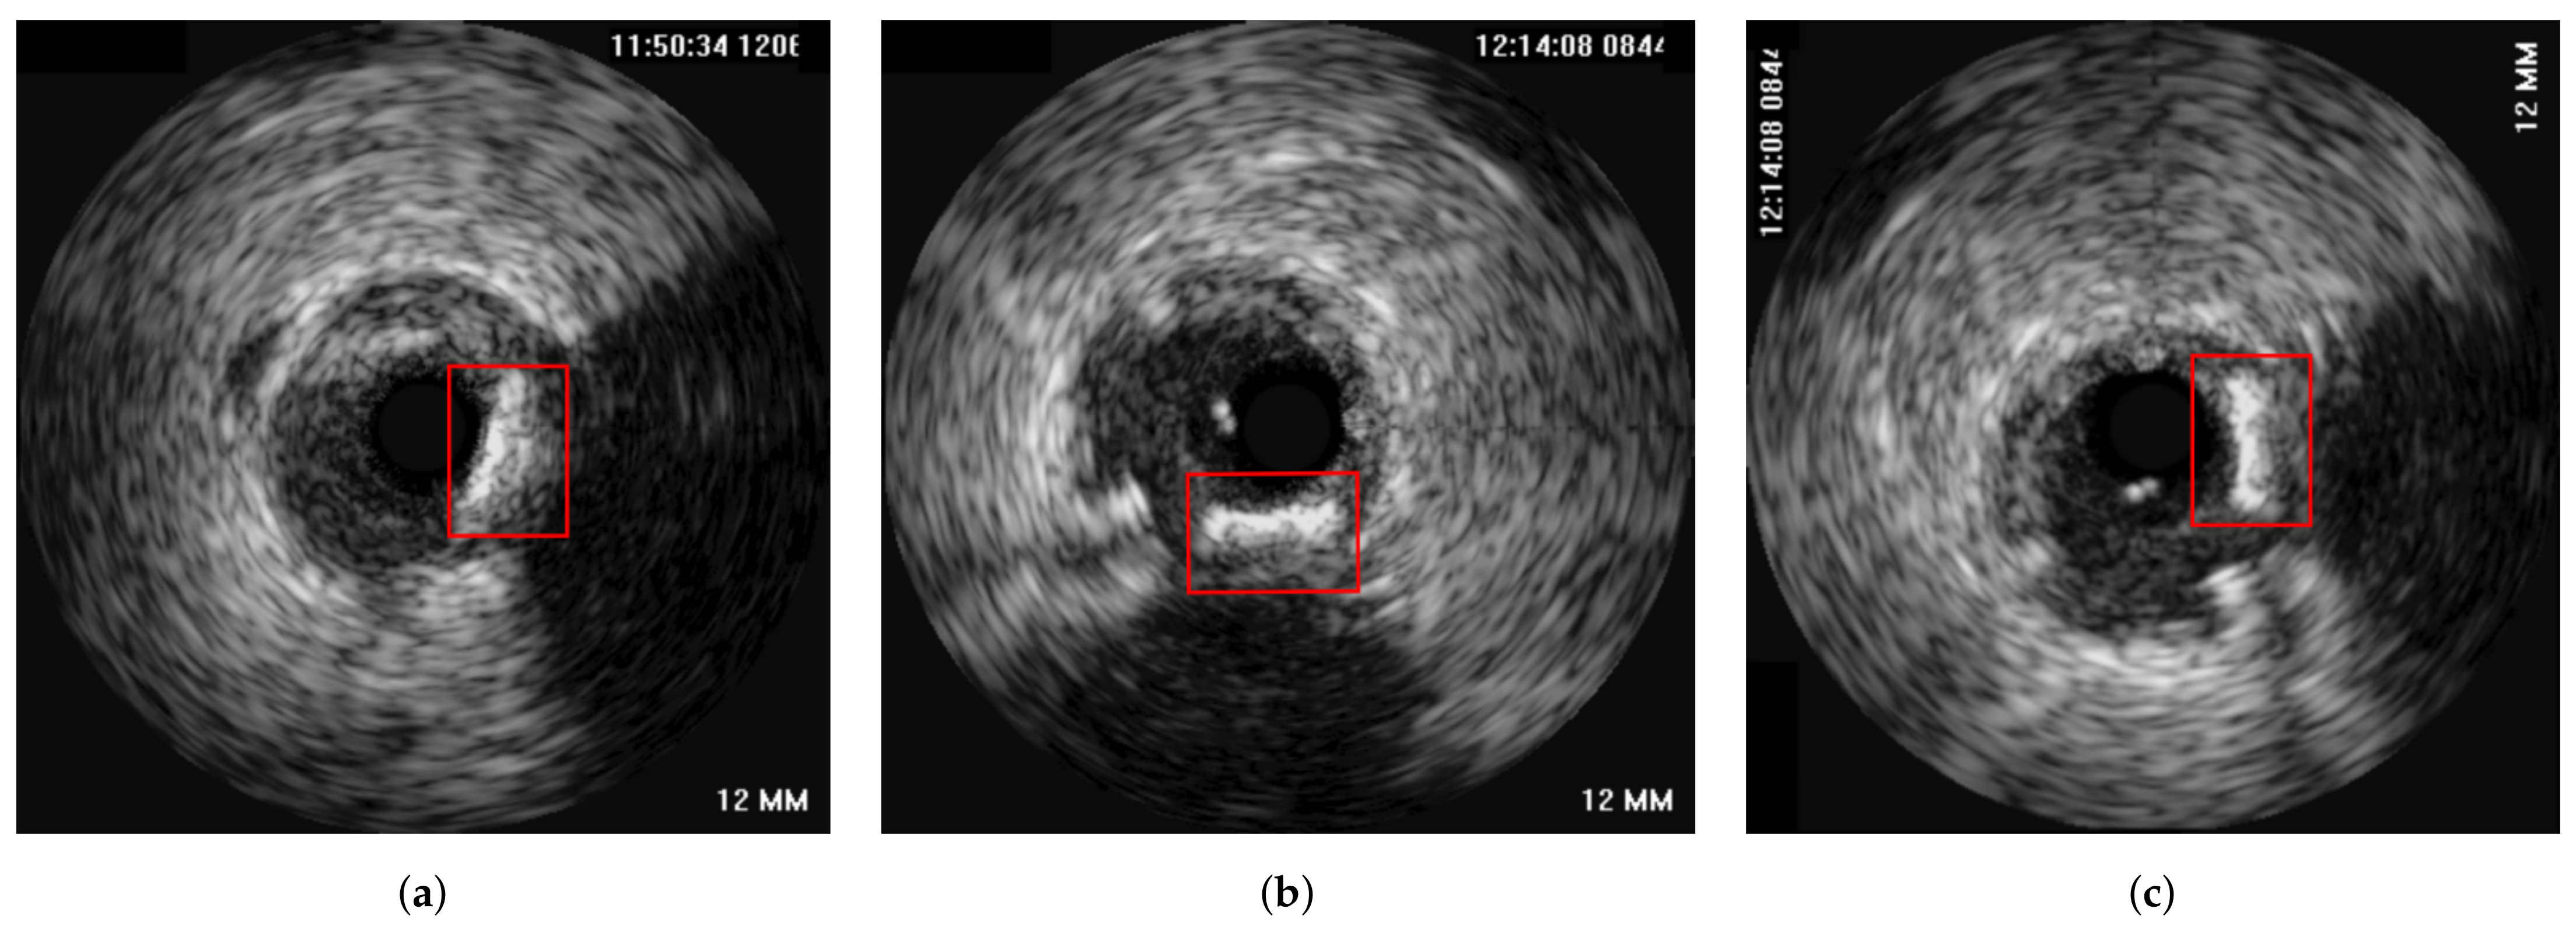

4.2. Experiments on In-Vivo Data

- Mean MI of the corresponding frames in the overlap of the unregistered end-diastolic IVUS pullbacks starting from the first frame of each sequence. (blue)

- Mean MI of the matched frames of the longitudinally registered sequences. (red)

- Mean MI of the 2D (axially) registered frame pairs of the longitudinally registered sequences. (grey)